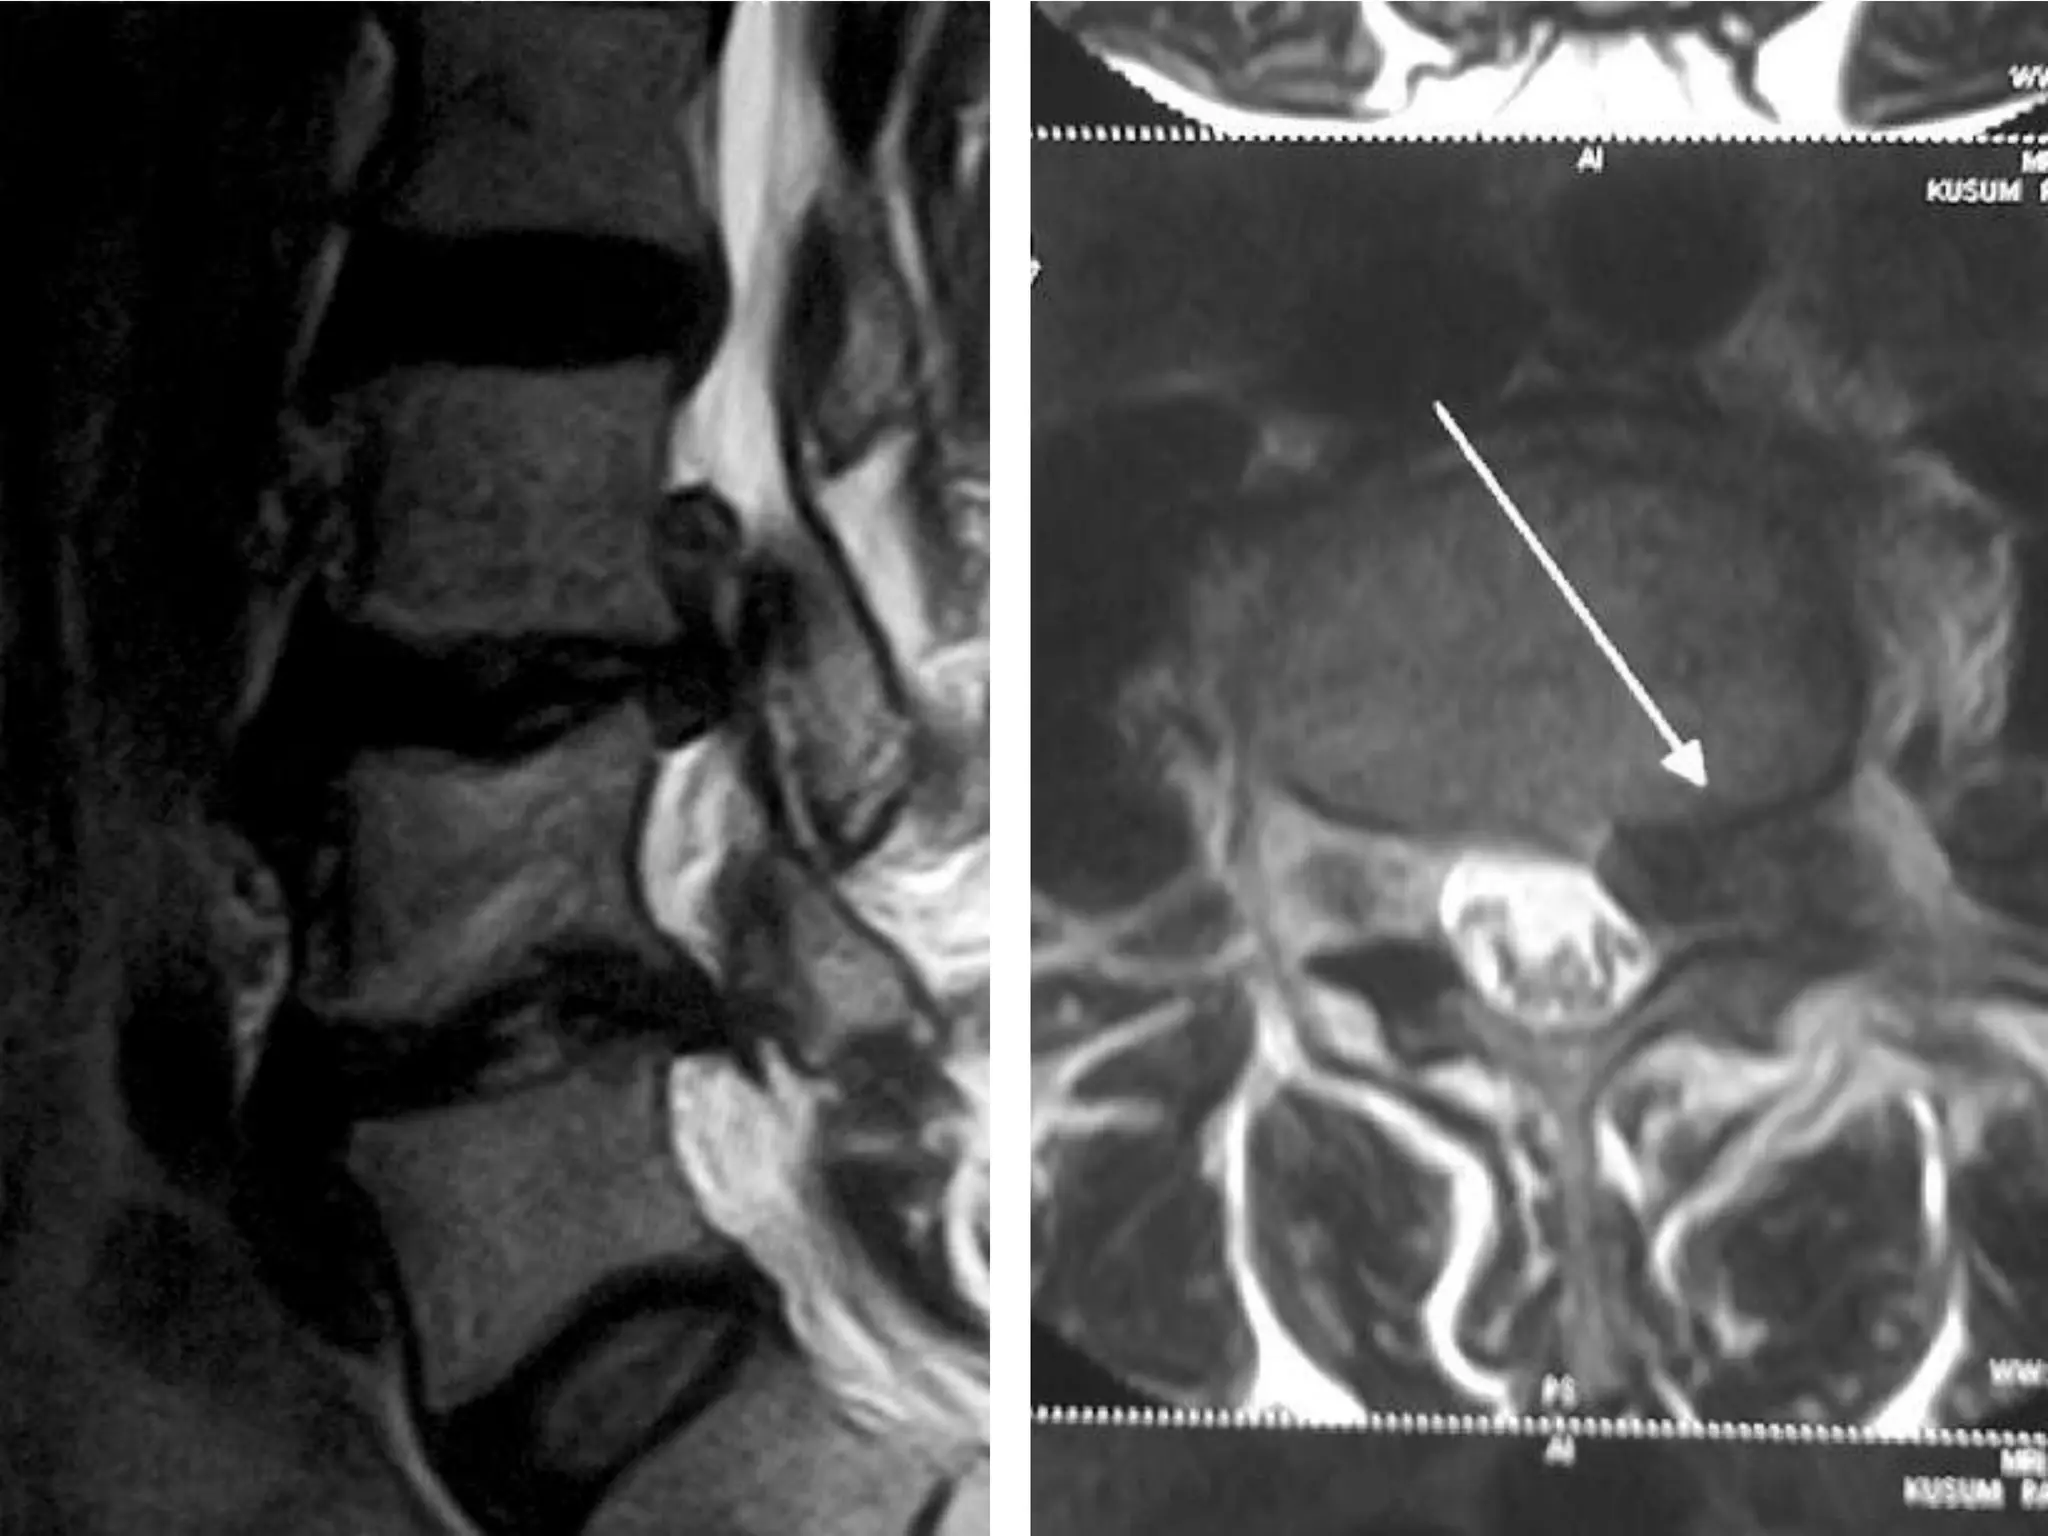

Dynamic Degenerative InstabilityFlexionExtension